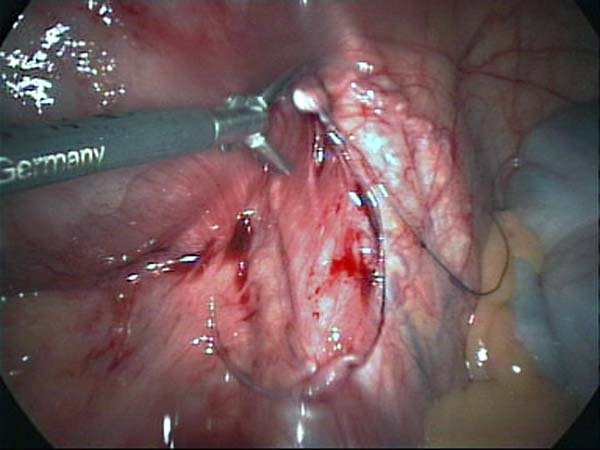

- Laparoscopy Photos 1

- Laparoscopy Photos 2

- Laparoscopy Photos 3

- Laparoscopy Photos 4

Laparoscopy Photos Polycystic Ovaries adhesiolysis IUCD Through Uterine Wall | Dr N Layyous